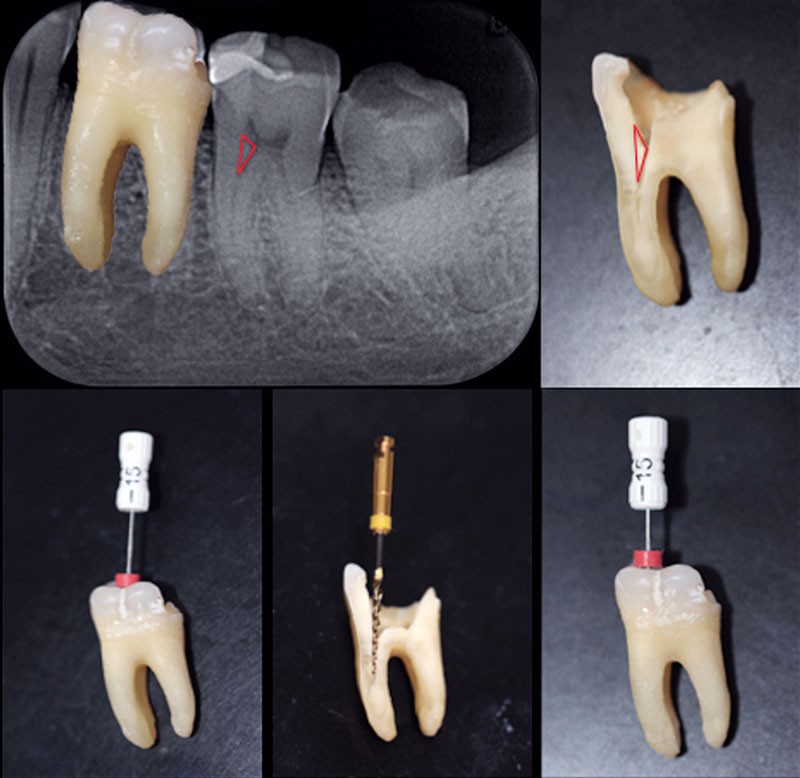

Triangle de Schilder

Les contraintes coronaires, particulièrement représentées par les triangles dentinaires, présents à la jonction entre la chambre et le canal, également appelés triangles de Schilder (fig. 1), s’opposent à la pénétration des instruments et exercent sur ces derniers des forces pouvant, dans le meilleur des cas, freiner leur pénétration apicale et, dans le pire, conduire à la fracture instrumentale.

C’est l’élimination totale des contraintes coronaires qui facilitera l’accès au tiers apical du canal en supprimant le triangle de dentine coronaire qui gène la progression des instruments dans l’axe du canal.

Les évaseurs permettent de supprimer ces triangles internes de dentine. Cette procédure facilite l’instrumentation ultérieure. L’évasement du tiers coronaire du canal est une décision stratégique qui influence toutes les étapes ultérieures de traitement.